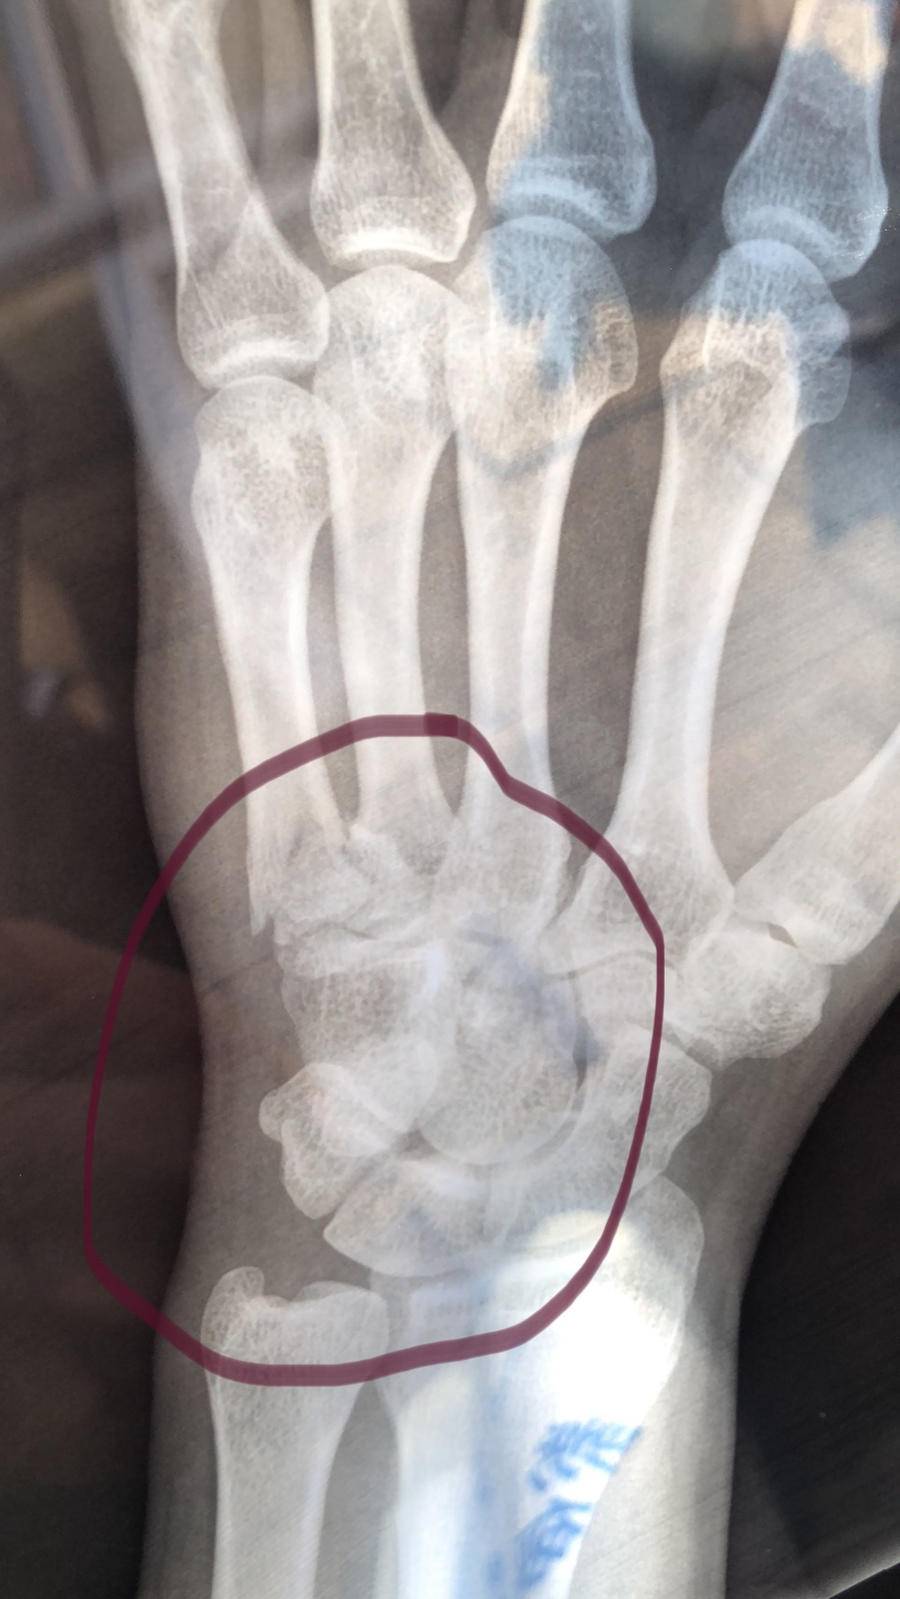

等到将程某带回时,张玉春才感觉到左手疼痛,不久后,左手就肿胀了起来。后来到医院检查,被诊断为左手第5掌骨基底部骨折。

“后来医生仔细看了看,发现我的手掌一处已经出现了粉碎性骨折。”19日,做完手术刚刚回家休养的张玉春谈及自己的伤情时,口气显得很轻松。实际上,在手术中,他的掌骨上被打上了钢钉,光缝针就缝了十几针。